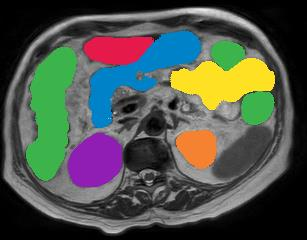

Vision transformers, with their ability to more efficiently model long-range context, have demonstrated impressive accuracy gains in several computer vision and medical image analysis tasks including segmentation. However, such methods need large labeled datasets for training, which is hard to obtain for medical image analysis. Self-supervised learning (SSL) has demonstrated success in medical image segmentation using convolutional networks. In this work, we developed a \underline{s}elf-distillation learning with \underline{m}asked \underline{i}mage modeling method to perform SSL for vision \underline{t}ransformers (SMIT) applied to 3D multi-organ segmentation from CT and MRI. Our contribution is a dense pixel-wise regression within masked patches called masked image prediction, which we combined with masked patch token distillation as pretext task to pre-train vision transformers. We show our approach is more accurate and requires fewer fine tuning datasets than other pretext tasks. Unlike prior medical image methods, which typically used image sets arising from disease sites and imaging modalities corresponding to the target tasks, we used 3,643 CT scans (602,708 images) arising from head and neck, lung, and kidney cancers as well as COVID-19 for pre-training and applied it to abdominal organs segmentation from MRI pancreatic cancer patients as well as publicly available 13 different abdominal organs segmentation from CT. Our method showed clear accuracy improvement (average DSC of 0.875 from MRI and 0.878 from CT) with reduced requirement for fine-tuning datasets over commonly used pretext tasks. Extensive comparisons against multiple current SSL methods were done. Code will be made available upon acceptance for publication.